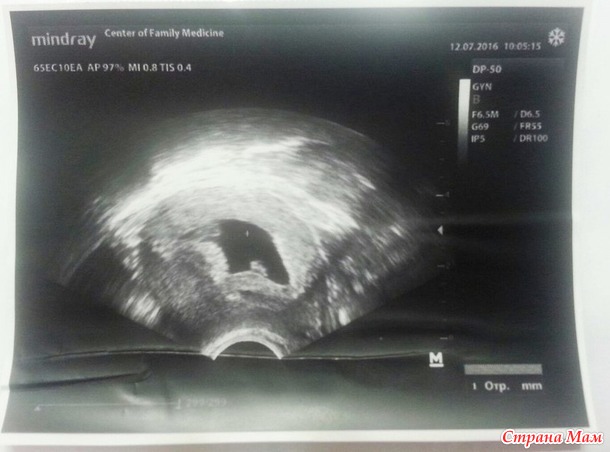

На узи сказали, что у меня моноамниотическая двойня.. Делала на 7ой неделе беременности. КТР 1 эмбриона - 6,6мм, КТР 2 эмбриона- 9,2мм. СБ++ Детки находятся на разных полюсах скажем так..